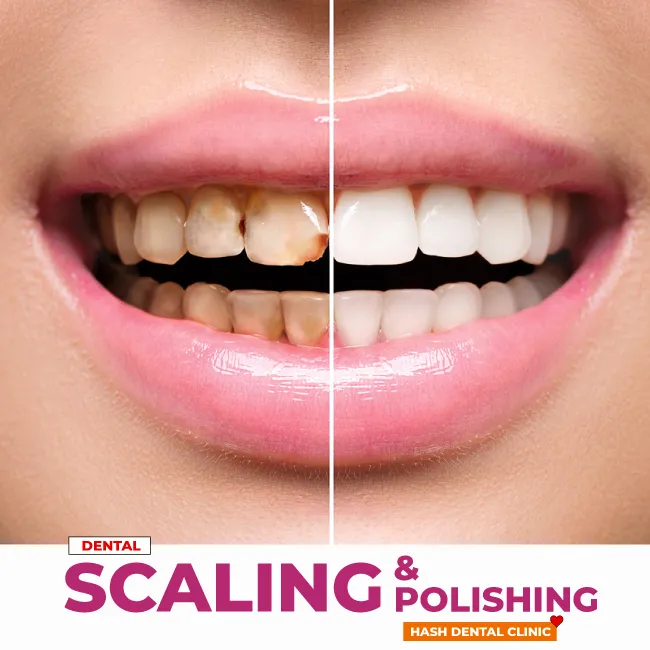

Scaling & Polishing

- Scaling: Using specialized instruments, the dentist carefully scrapes away plaque and tartar from tooth surfaces and below the gumline.

- Polishing: A rotating rubber cup attached to a dental handpiece is used to apply a polishing paste to the teeth. This paste helps remove surface stains and leaves teeth smooth and shiny.

- Brighter Smile: Polishing makes teeth smoother, brighter, and removes surface stains.